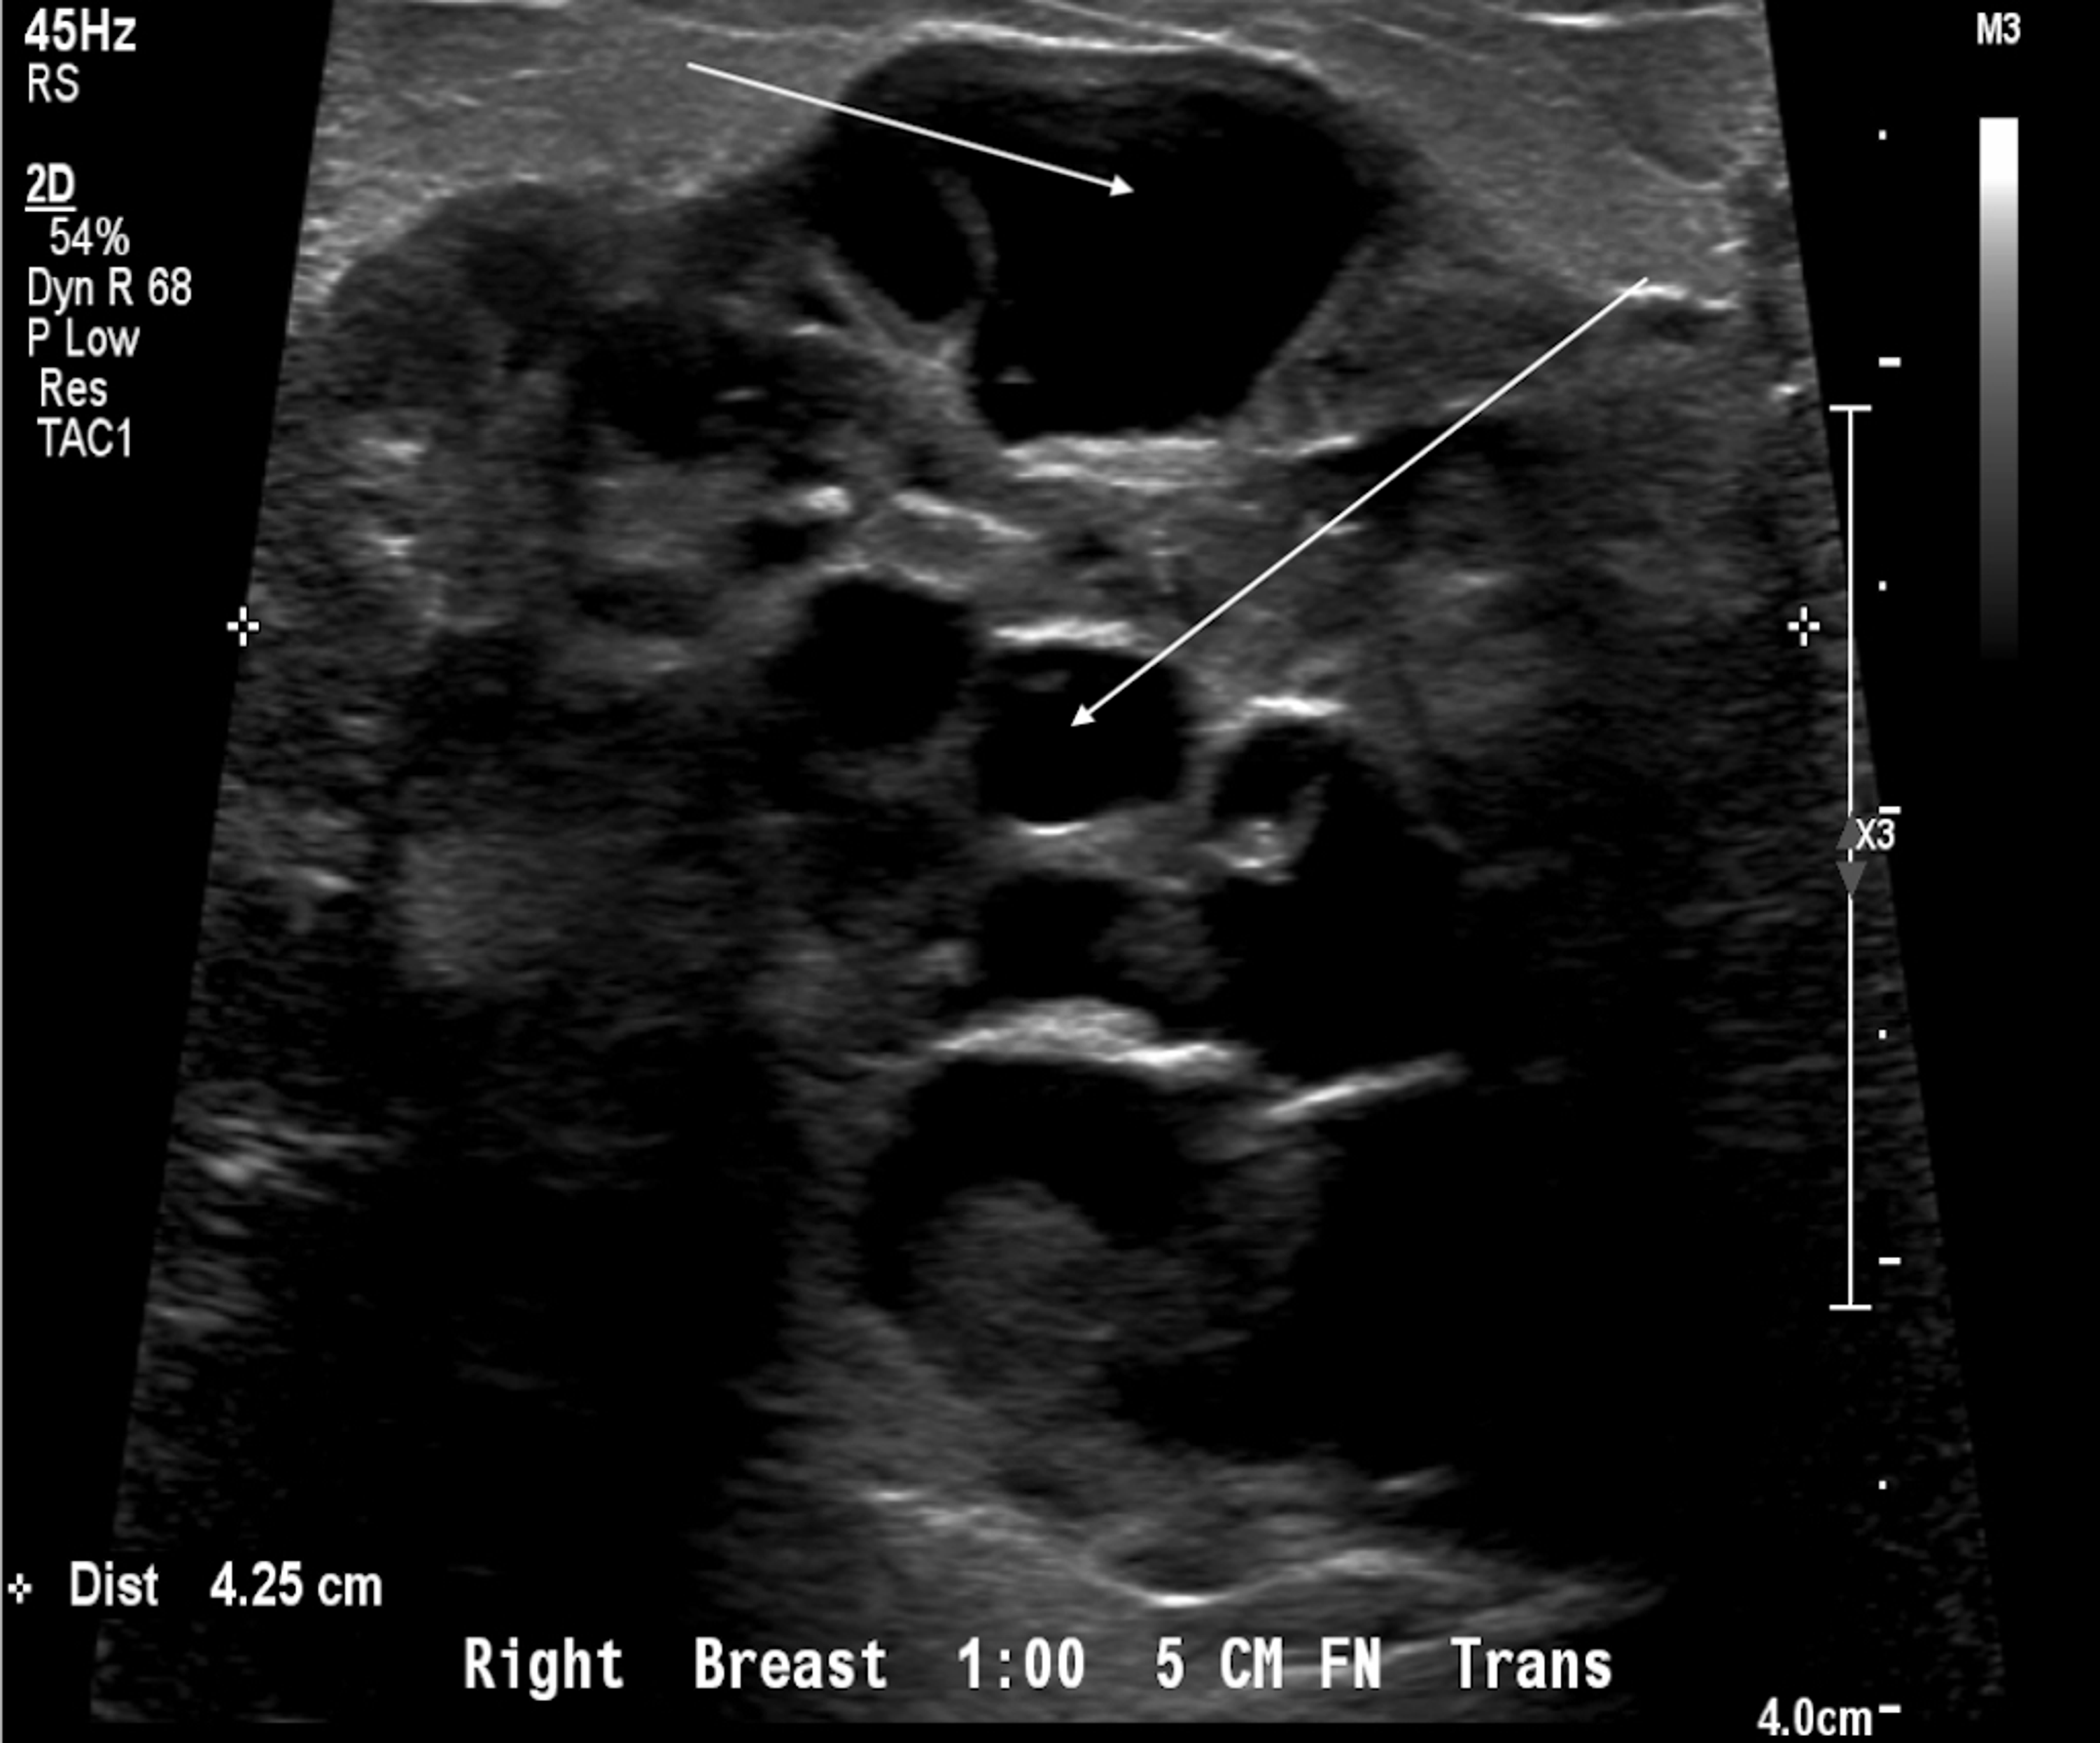

Cureus Metaplastic Breast Carcinoma Presenting as a Mixed Solid and Internal Ultrasound Showed Nothing But what happens when your pregnancy test is positive, yet your ultrasound shows no signs of a baby? A pregnancy that doesn't show on an ultrasound scan is called a 'pregnancy of unknown location'. Unfortunately, it's possible to have a positive pregnancy test but no baby on the ultrasound. If you’re in this situation, you might be saying to yourself,. Internal Ultrasound Showed Nothing.